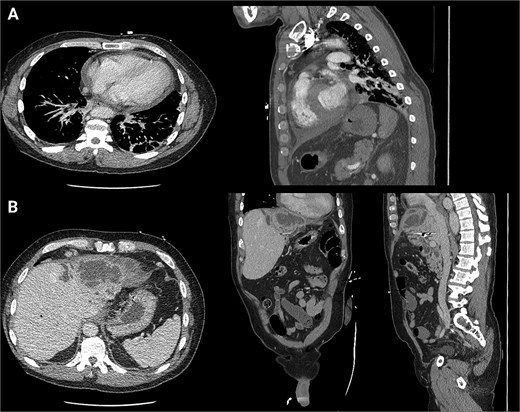

The patient presented the following day with fevers and new chest pain. He underwent a computed tomography angiography (CTA) chest and abdomen/pelvis, which revealed a left lower lobe consolidation and a moderate pericardial effusion. His hepatic abscess had increased in size to 7.2 × 5.5 cm (Fig. 2). Cardiology was consulted, and a bedside echo was performed, which found acute pericarditis. He was admitted and started on IV antibiotics and colchicine for his pericarditis. GI subsequently performed an ERCP, which showed no biliary or anastomotic stricture (Fig. 3). It was thought that it was likely a choledochal cyst, and the plan was for elective left hepatectomy. He was transitioned to oral antibiotics and discharged with colchicine for 3 months.

First readmission CT scans. (A) CTA chest images in the axial and sagittal planes illustrating the newly developed pericardial effusion. (B) CTA abdomen/pelvis images in the axial, coronal, and sagittal planes. These illustrate the abscess increasing in size.